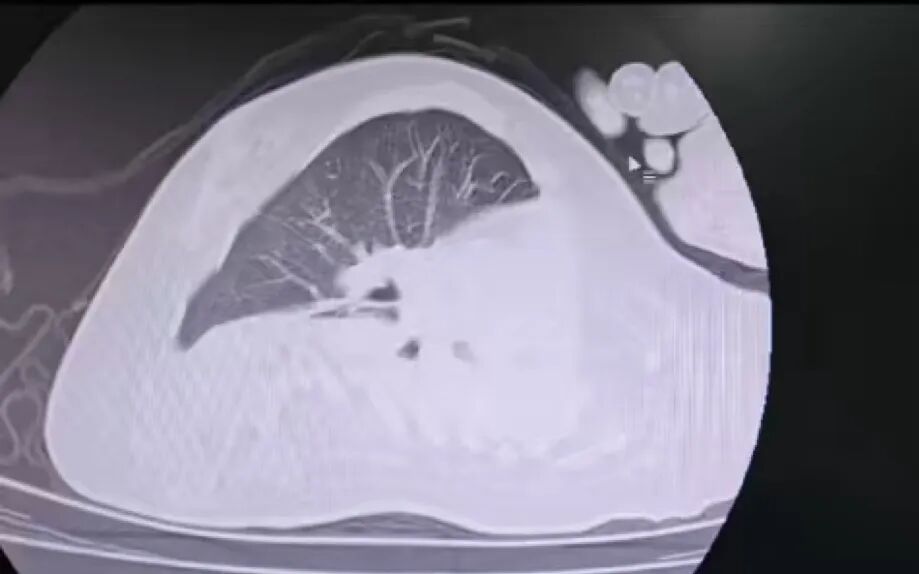

治療前

治療后